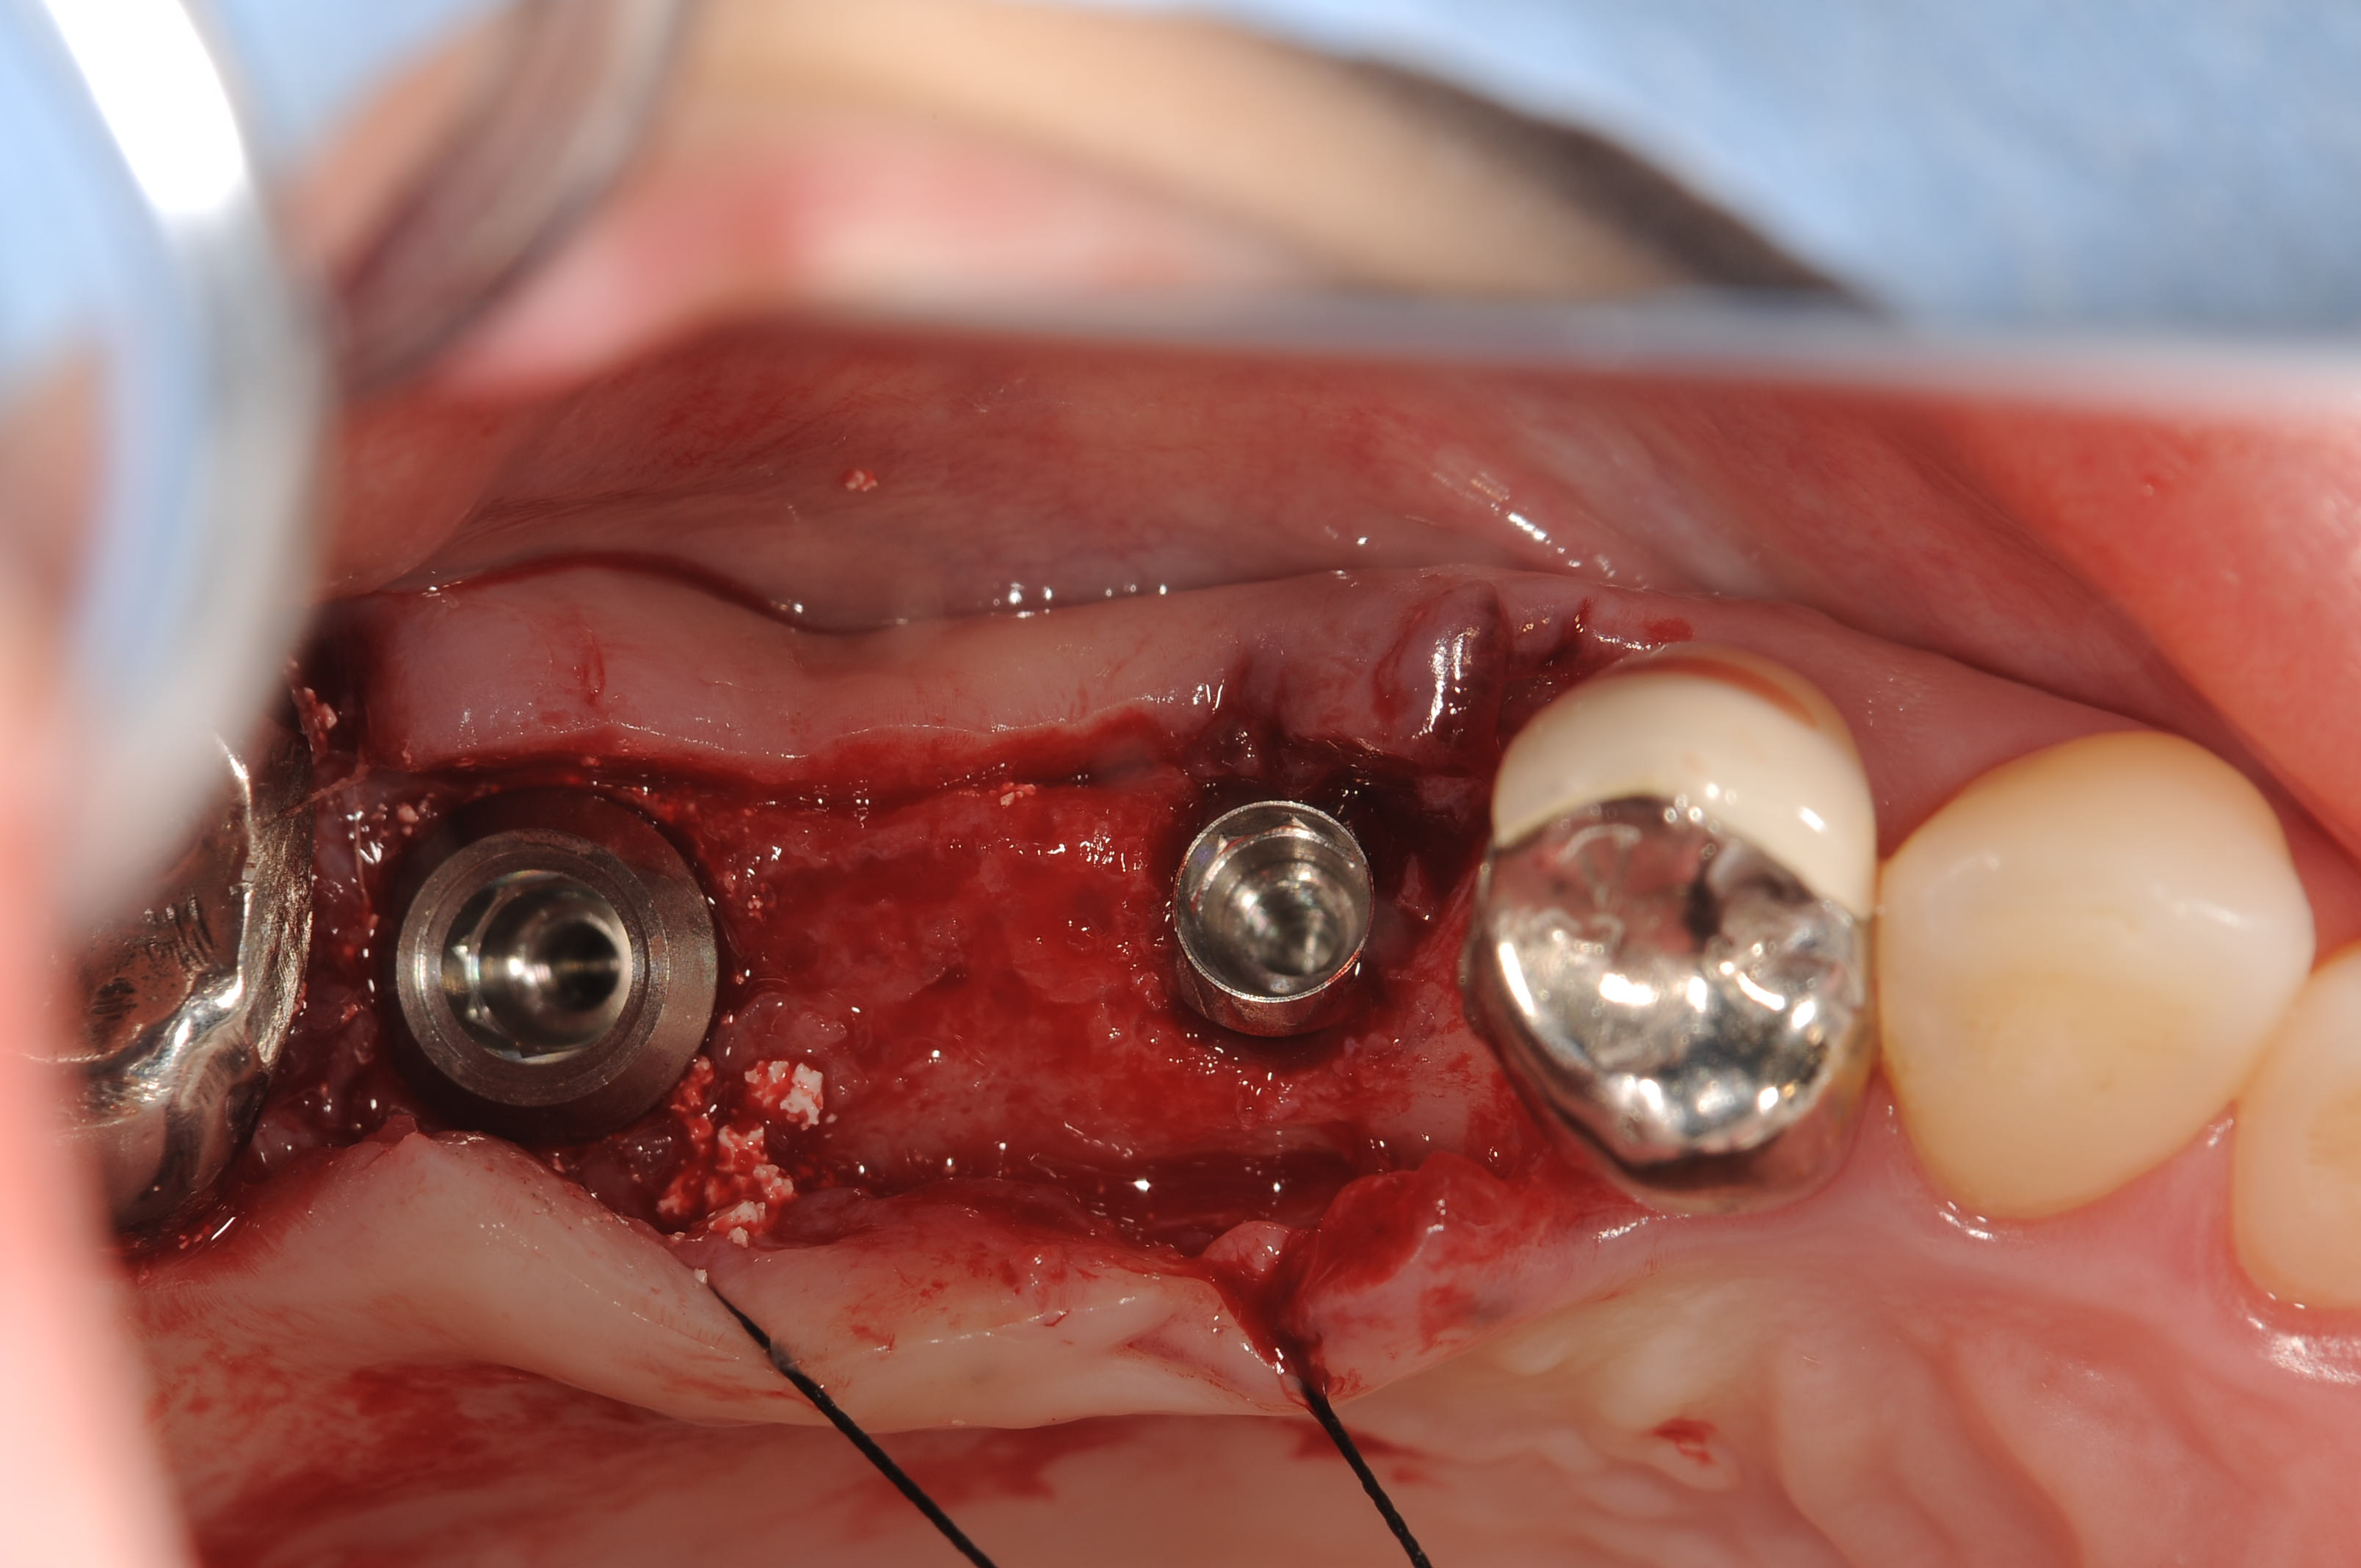

今日のオペは、上顎左側の567欠損部位に、サイブロンプロEXを2本埋入しました。

5番部位は、RN11mmを7番部位はWN11mmをそれぞれ埋入しました。

初期固定も問題なく、プラットフォームスイッチのヒーリングアバット装着して、1回法で終了です。

フィクスチャー埋入後です。